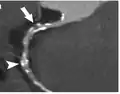

CT-Angiographie; mittels multiplanarer Reformation (hier die sog. curved MPR) sind auch Schnittdarstellungen entlang beliebiger Gefäßverläufe möglich, wodurch die gezeigte Arteriosklerose sehr gut visualisiert werden kann.

CT-Angiographie; mittels multiplanarer Reformation (hier die sog. curved MPR) sind auch Schnittdarstellungen entlang beliebiger Gefäßverläufe möglich, wodurch die gezeigte Arteriosklerose sehr gut visualisiert werden kann.